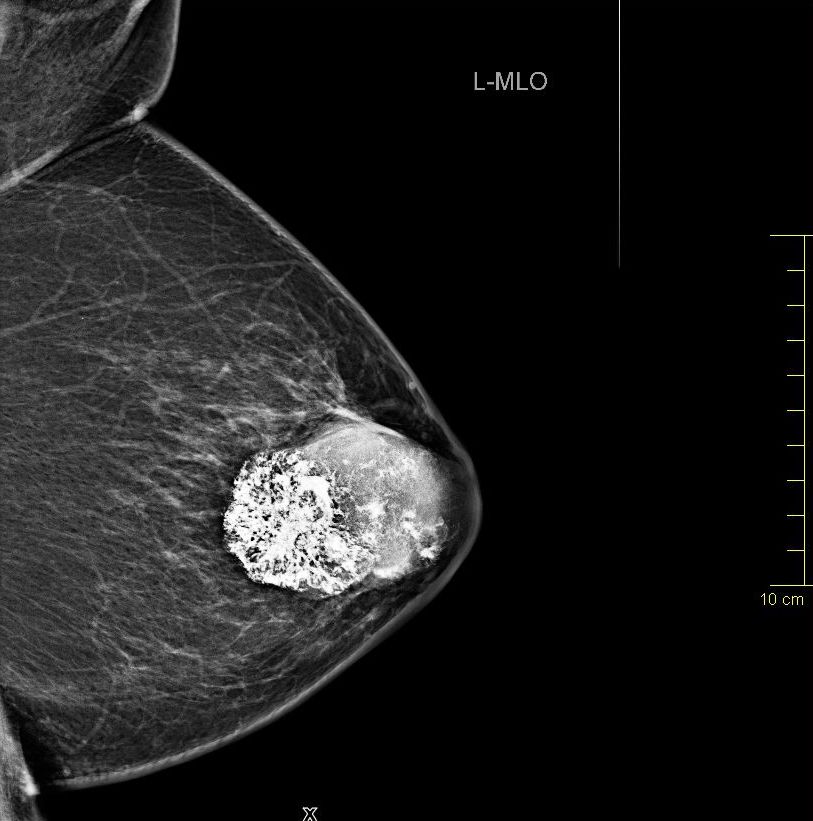

| Fall | 72-jährige Frau, bei der vor 5 Jahren ein gutartiger Tumor diagnostiziert wurde. Vor 8 Monaten war der Tumor auf 4cm angewachsen. Die Exzision wurde empfohlen. Jetzt war der Tumor 66 mm groß, sehr hart und teilweise verkalkt. | |||

| vor OP | Mammographie links MLO.![]() |

Vergrößerung.![]() | ||